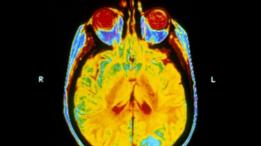

تُعالج أورام المخ الثانوية في مرضى سرطان الرئة عادة بالعلاج الإشعاعي لكامل المخ.

وتُعالج أورام المخ الثانوية، وهي التي تظهر نتيجة سرطان في عضو آخر غير المخ، عادة باستخدام العلاج الإشعاعي الشامل للمخ، إلى جانب المركبات العضوية ووسائل علاج أخرى، وذلك لخفض الآثار الجانبية لعلاج السرطان.